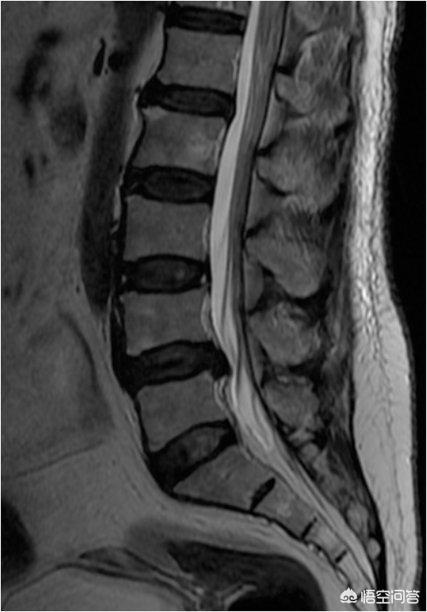

上の写真は、椎間板が位置によって異なる力を受けていることを示すものである。より正確かつ具体的に言えば、小さなゼリー(髄核)は、椎間板に作用する非対称の圧力にさらされている。前かがみになると髄核への圧力が髄核を後方に押しやり、体を後ろに傾けると、前かがみとは逆に髄核が前方に押し出される。そのため、前かがみになったときだけ髄核への圧力が過剰になり、ヘルニアが大きくなるのです。横になっているときは、基本的に圧力はなく、隆起に変化はありません。

長年の診療の中で、私はあまりにも多くの腰椎前突の患者さんを見てきましたが、その中には何の症状もない腰椎前突の患者さんも多く、部外者から見ると信じられないような患者さんもいます!多くの患者は、初期の段階では激しい痛みがあり、一定期間の保存的治療の後、症状は徐々に緩和され、あるいは消失しますが、MRI検査を受けると、腰椎椎間板ヘルニアが縮小していないことが判明することがあります。